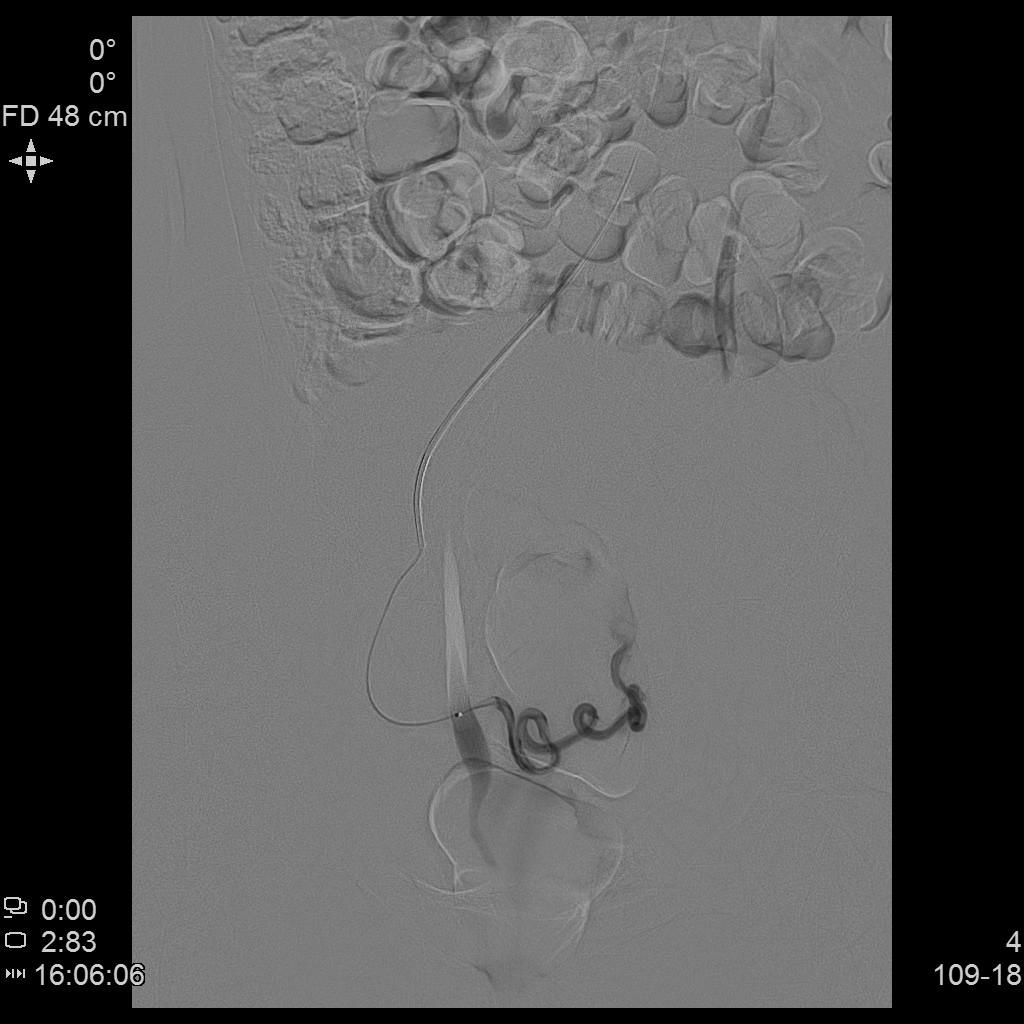

- 进一步超选插管左侧髂内动脉造影确认子动脉开口位置。

左侧髂内动脉造影

- 微导管进一步超选插管左侧子宫动脉主干造影确认位置。

左侧子宫动脉造影